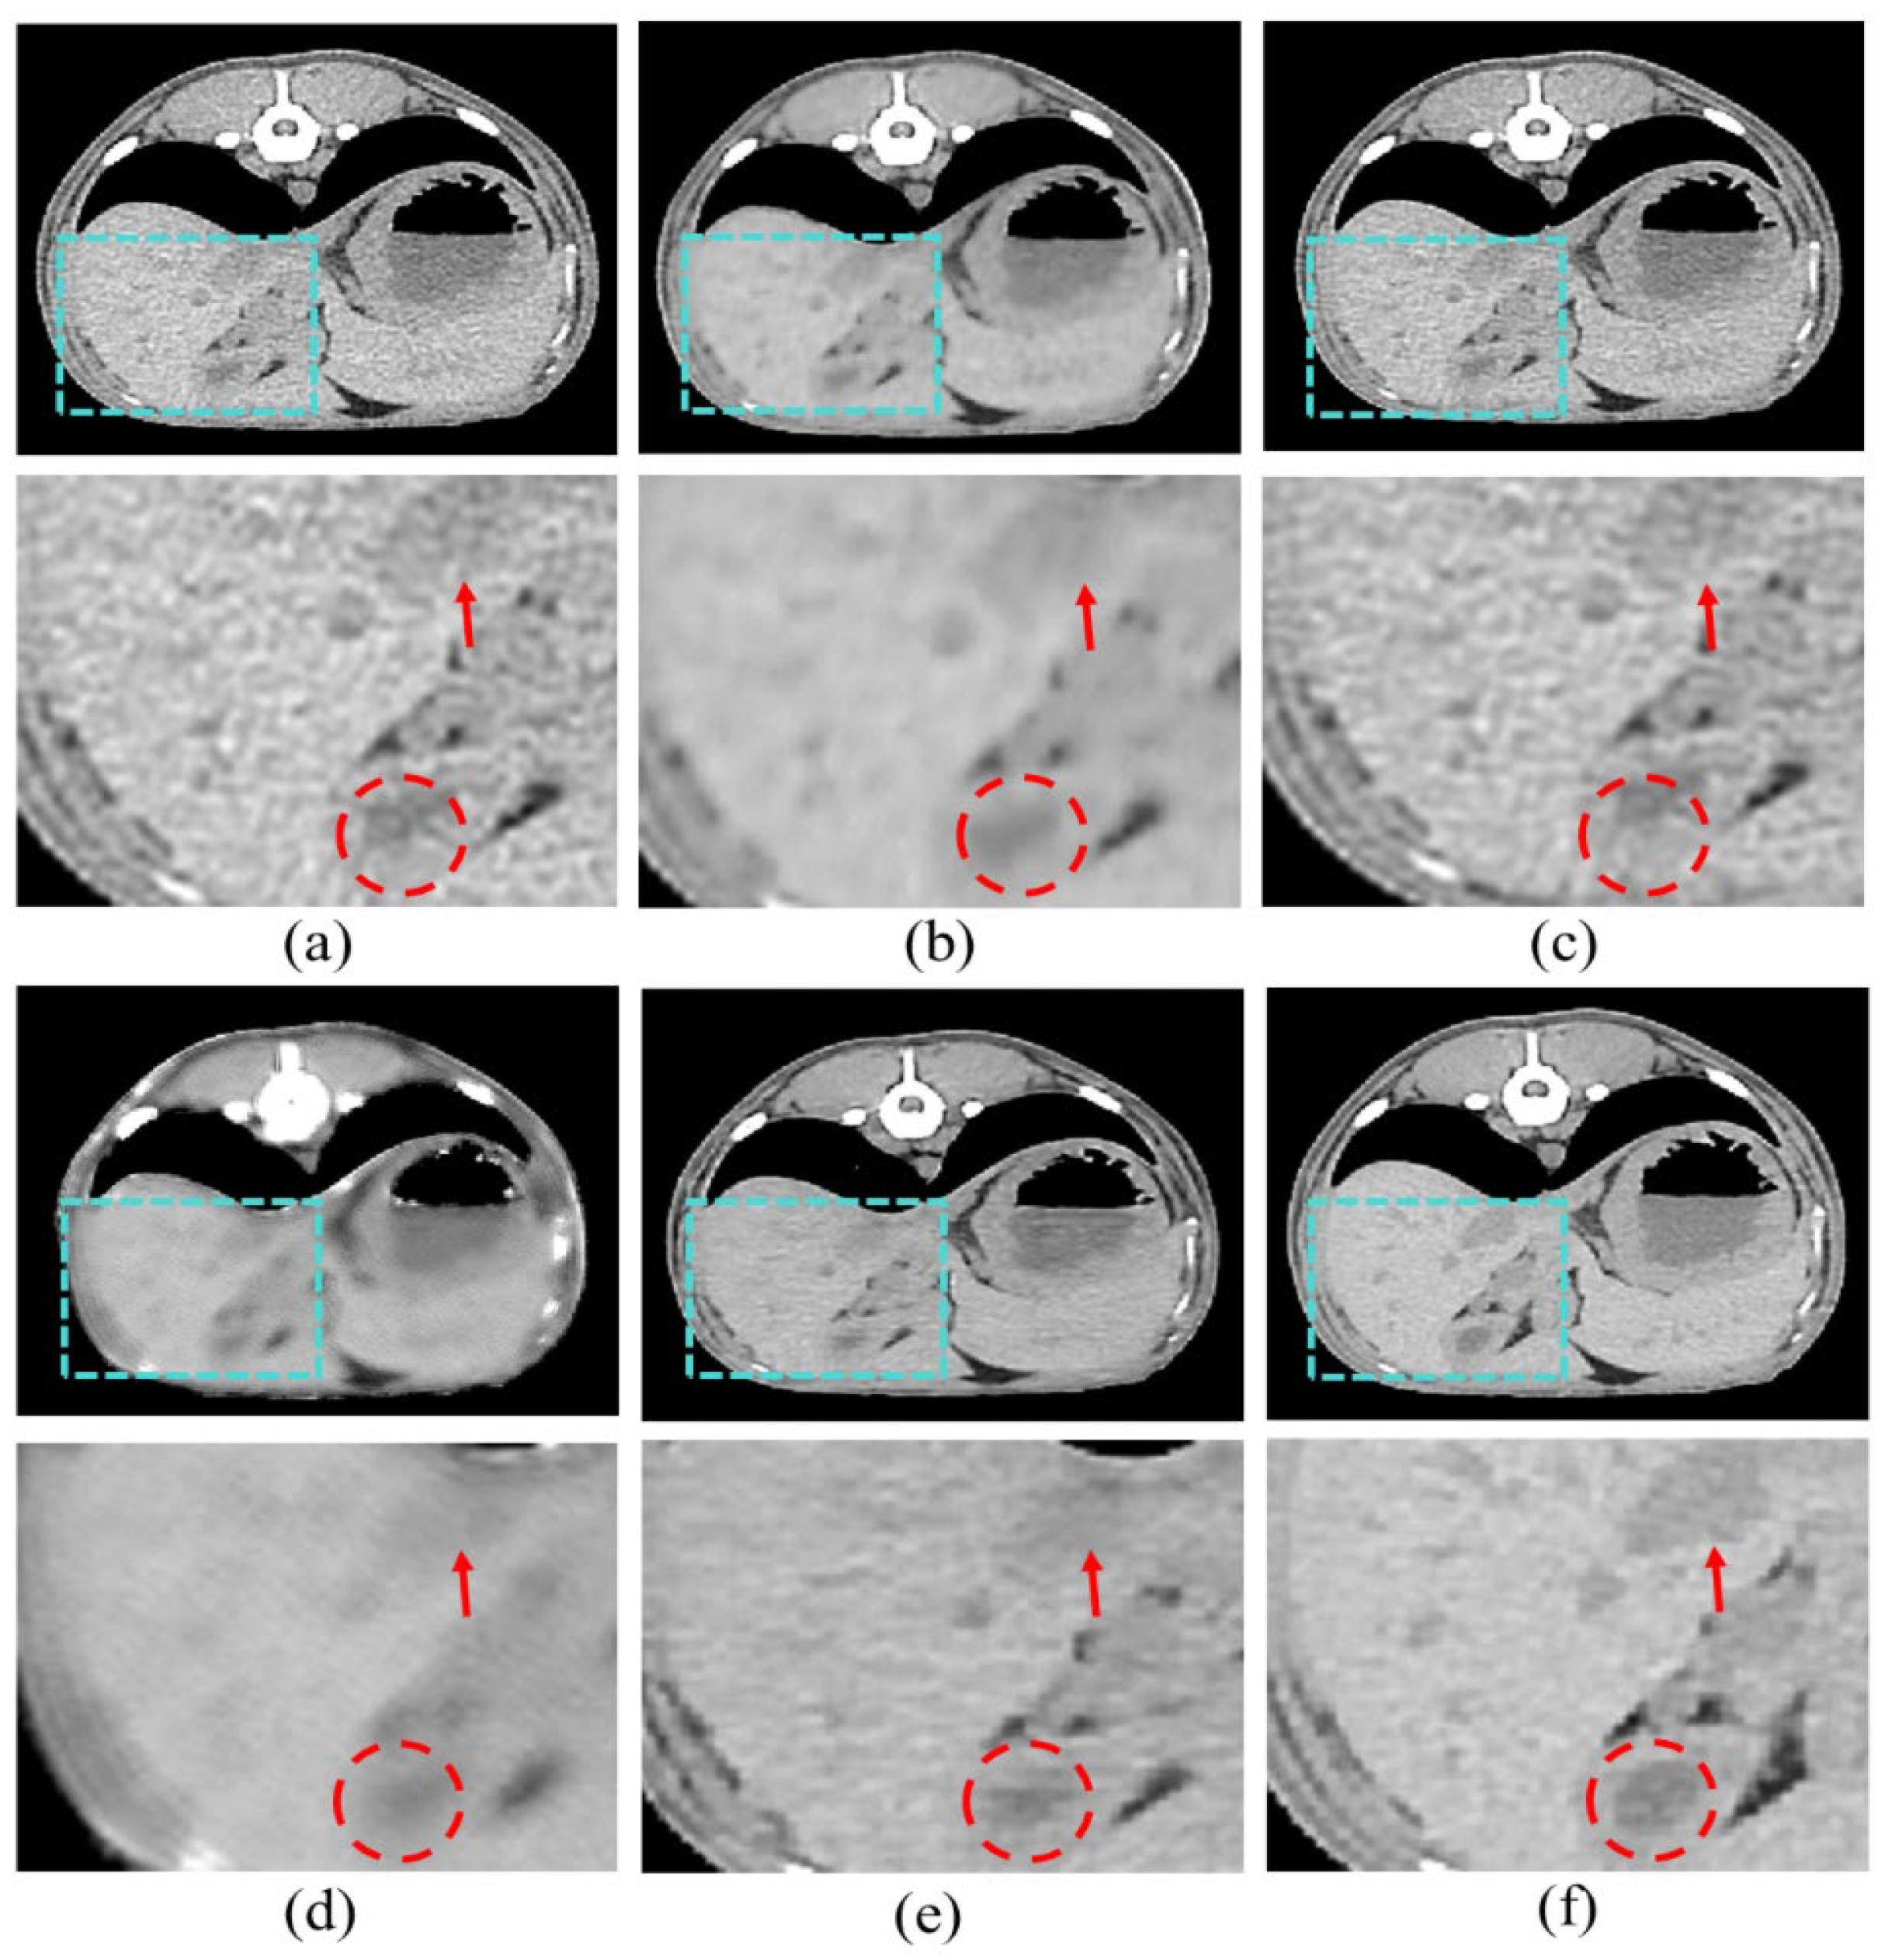

We adopted scSE blocks to maximize the performance of the HFS modules. In this section, we performed three ablation studies to validate the effectiveness of scSE. We compared cSE alone, sSE alone, and the scSE method, which combines cSE and sSE. Each method was evaluated based on whether it applied spatial squeeze and channel excitation or channel squeeze and spatial excitation, and we identified and described the features of each approach. First, cSE alone emphasized useful channels by squeezing them along spatial regions and excitations along channels. The results are shown in Figure 6b and indicate reduced noise and improved perceptual quality compared to the conventional LDCT image. However, the contrast is still not sharp enough, and important structures are faintly visible. Second, sSE alone emphasizes pixel-wise information by spatially exciting them along the channel, as opposed to cSE. The results, shown in Figure 6c, demonstrate improved contrast, making anatomical structures more distinct. However, the reconstructed high-resolution image appears uneven and less smooth. Finally, the scSE method combines the advantages of both cSE and sSE. Figure 6d shows that scSE yields the most pronounced contrast, improving upon the limitations observed with sSE alone.

The quantitative evaluation of each item is shown in Table 1. Precision and recall are evaluated by truncation 1.0 and 0.3. Truncation is a technique used to sample the best images from the trained distribution after training the GAN with the truncation trick. The farther away from the mean of the distribution, the more transformed images will be sampled; close to 0 means sampling near the mean, and close to 1 means sampling from the distribution as it is. Low and standard dose are scores for comparison between the different methods. The scores when applying cSE, sSE, and scSE to the base model show positive results, indicating that LDCT can be used as input data to produce images close to SDCT. The highest and next highest scores in each area are shown in bold and underscore, respectively. scSE yielded the highest values for precision and recall. Precision was next highest with cSE, and recall was next highest after that with sSE. The proposed scSE method was found to be the most effective in both quantitative and perceptual evaluation.

Our results demonstrate that our proposed model outperforms comparative methods in both perceptual and quantitative evaluations. In our study, the results show that our model outperforms the comparative methods in both perceptual and quantitative evaluations in Figure 7 and Table 2. In addition, in Figure 6 and Table 1, the effectiveness of the proposed scSE method for denoising LDCT images in animal imaging was demonstrated. Through three ablation studies, we compared the performance of cSE alone, sSE alone, and the combined scSE method, revealing distinct advantages and limitations associated with each approach. The successful implementation of the scSE method underscores the importance of innovative approaches in addressing the challenges associated with LDCT imaging in veterinary medicine.

Figure 6. Ablation studies of the proposed method, (a) LDCT, (b) cSE alone, (c) sSE alone, (d) scSE, and (e) SDCT.